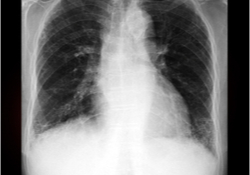

Wat is atelectase?

Atelectase betekent dat een deel van de long, of de hele long, geen lucht meer krijgt en samenvalt. De oorzaak is meestal een afsluiting (verstopping ) van één van de hoofdvertakkingen van de luchtwegen.